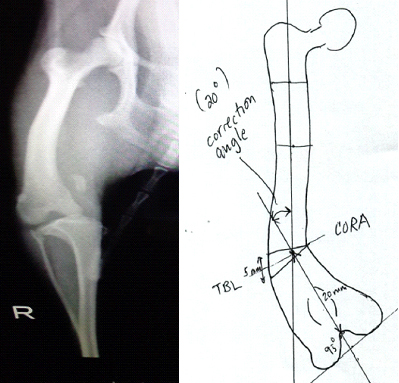

最後に上記の犬の膝蓋骨内側の脱臼(グレードⅣ)の手術計画の行程表の1例を示します。(Dr. Brian Beale.の指導による行程表)

- 大腿骨脛骨の矯正骨切り術